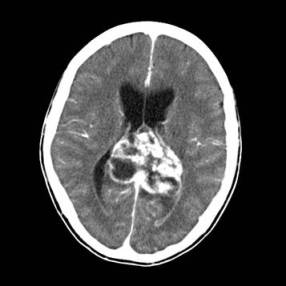

10、问答题

病历摘要:女性,59岁,胸闷、头晕2天,呈持续性,伴呕吐,以进食后明显。发现“高血压”10年,“糖尿病”2年。体格检查:血压70~210/30~120mmHg。

2.诊断依据是什么?